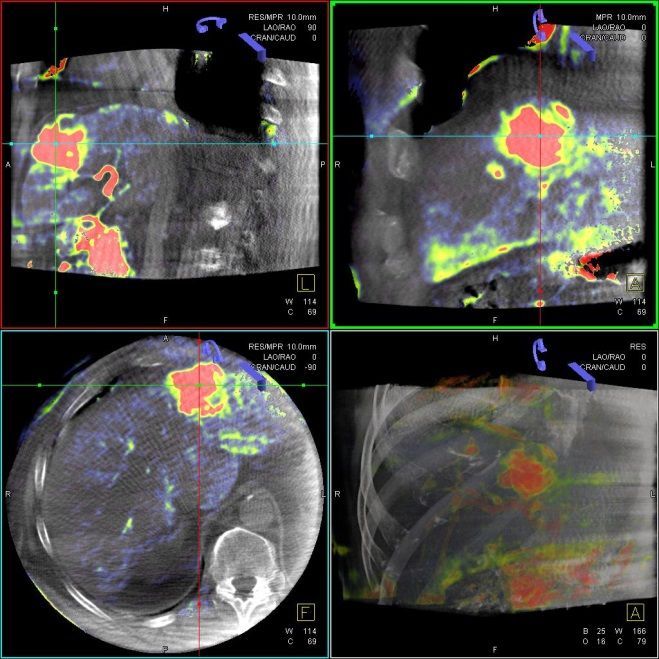

Die Selektive Interne Radiotherapie (SIRT) wird in der Fachliteratur auch Radioembolisation (RE) genannt. Hierbei werden gezielt kleine, radioaktive Kügelchen, sog. Mikrosphären, über den Katheter (siehe TACE) von mehreren Positionen in der Leber mit dem Blutstrom in das gut durchblutete Tumorgewebe gebracht und bleiben dort in den kleinen Gefäßen "stecken", die den Tumor ernähren. Von dort bestrahlt das in den Kügelchen enthaltene radioaktive Element Yttrium-90 über mehrere Tage hinweg das Tumorgewebe und zerstört es selektiv. Dieses Verfahren kann bei Leberkrebs oder -metastasen eingesetzt werden, wenn die Herde trotz Chemotherapie weiter wachsen und nicht chirurgisch oder mittels RFA und TACE behandelbar sind.

Das Verfahren wird von der interventionellen Radiologie zusammen mit der Partnerabteilung der Nuklearmedizin sowie den entsprechenden Partnerkliniken geplant und durchgeführt.